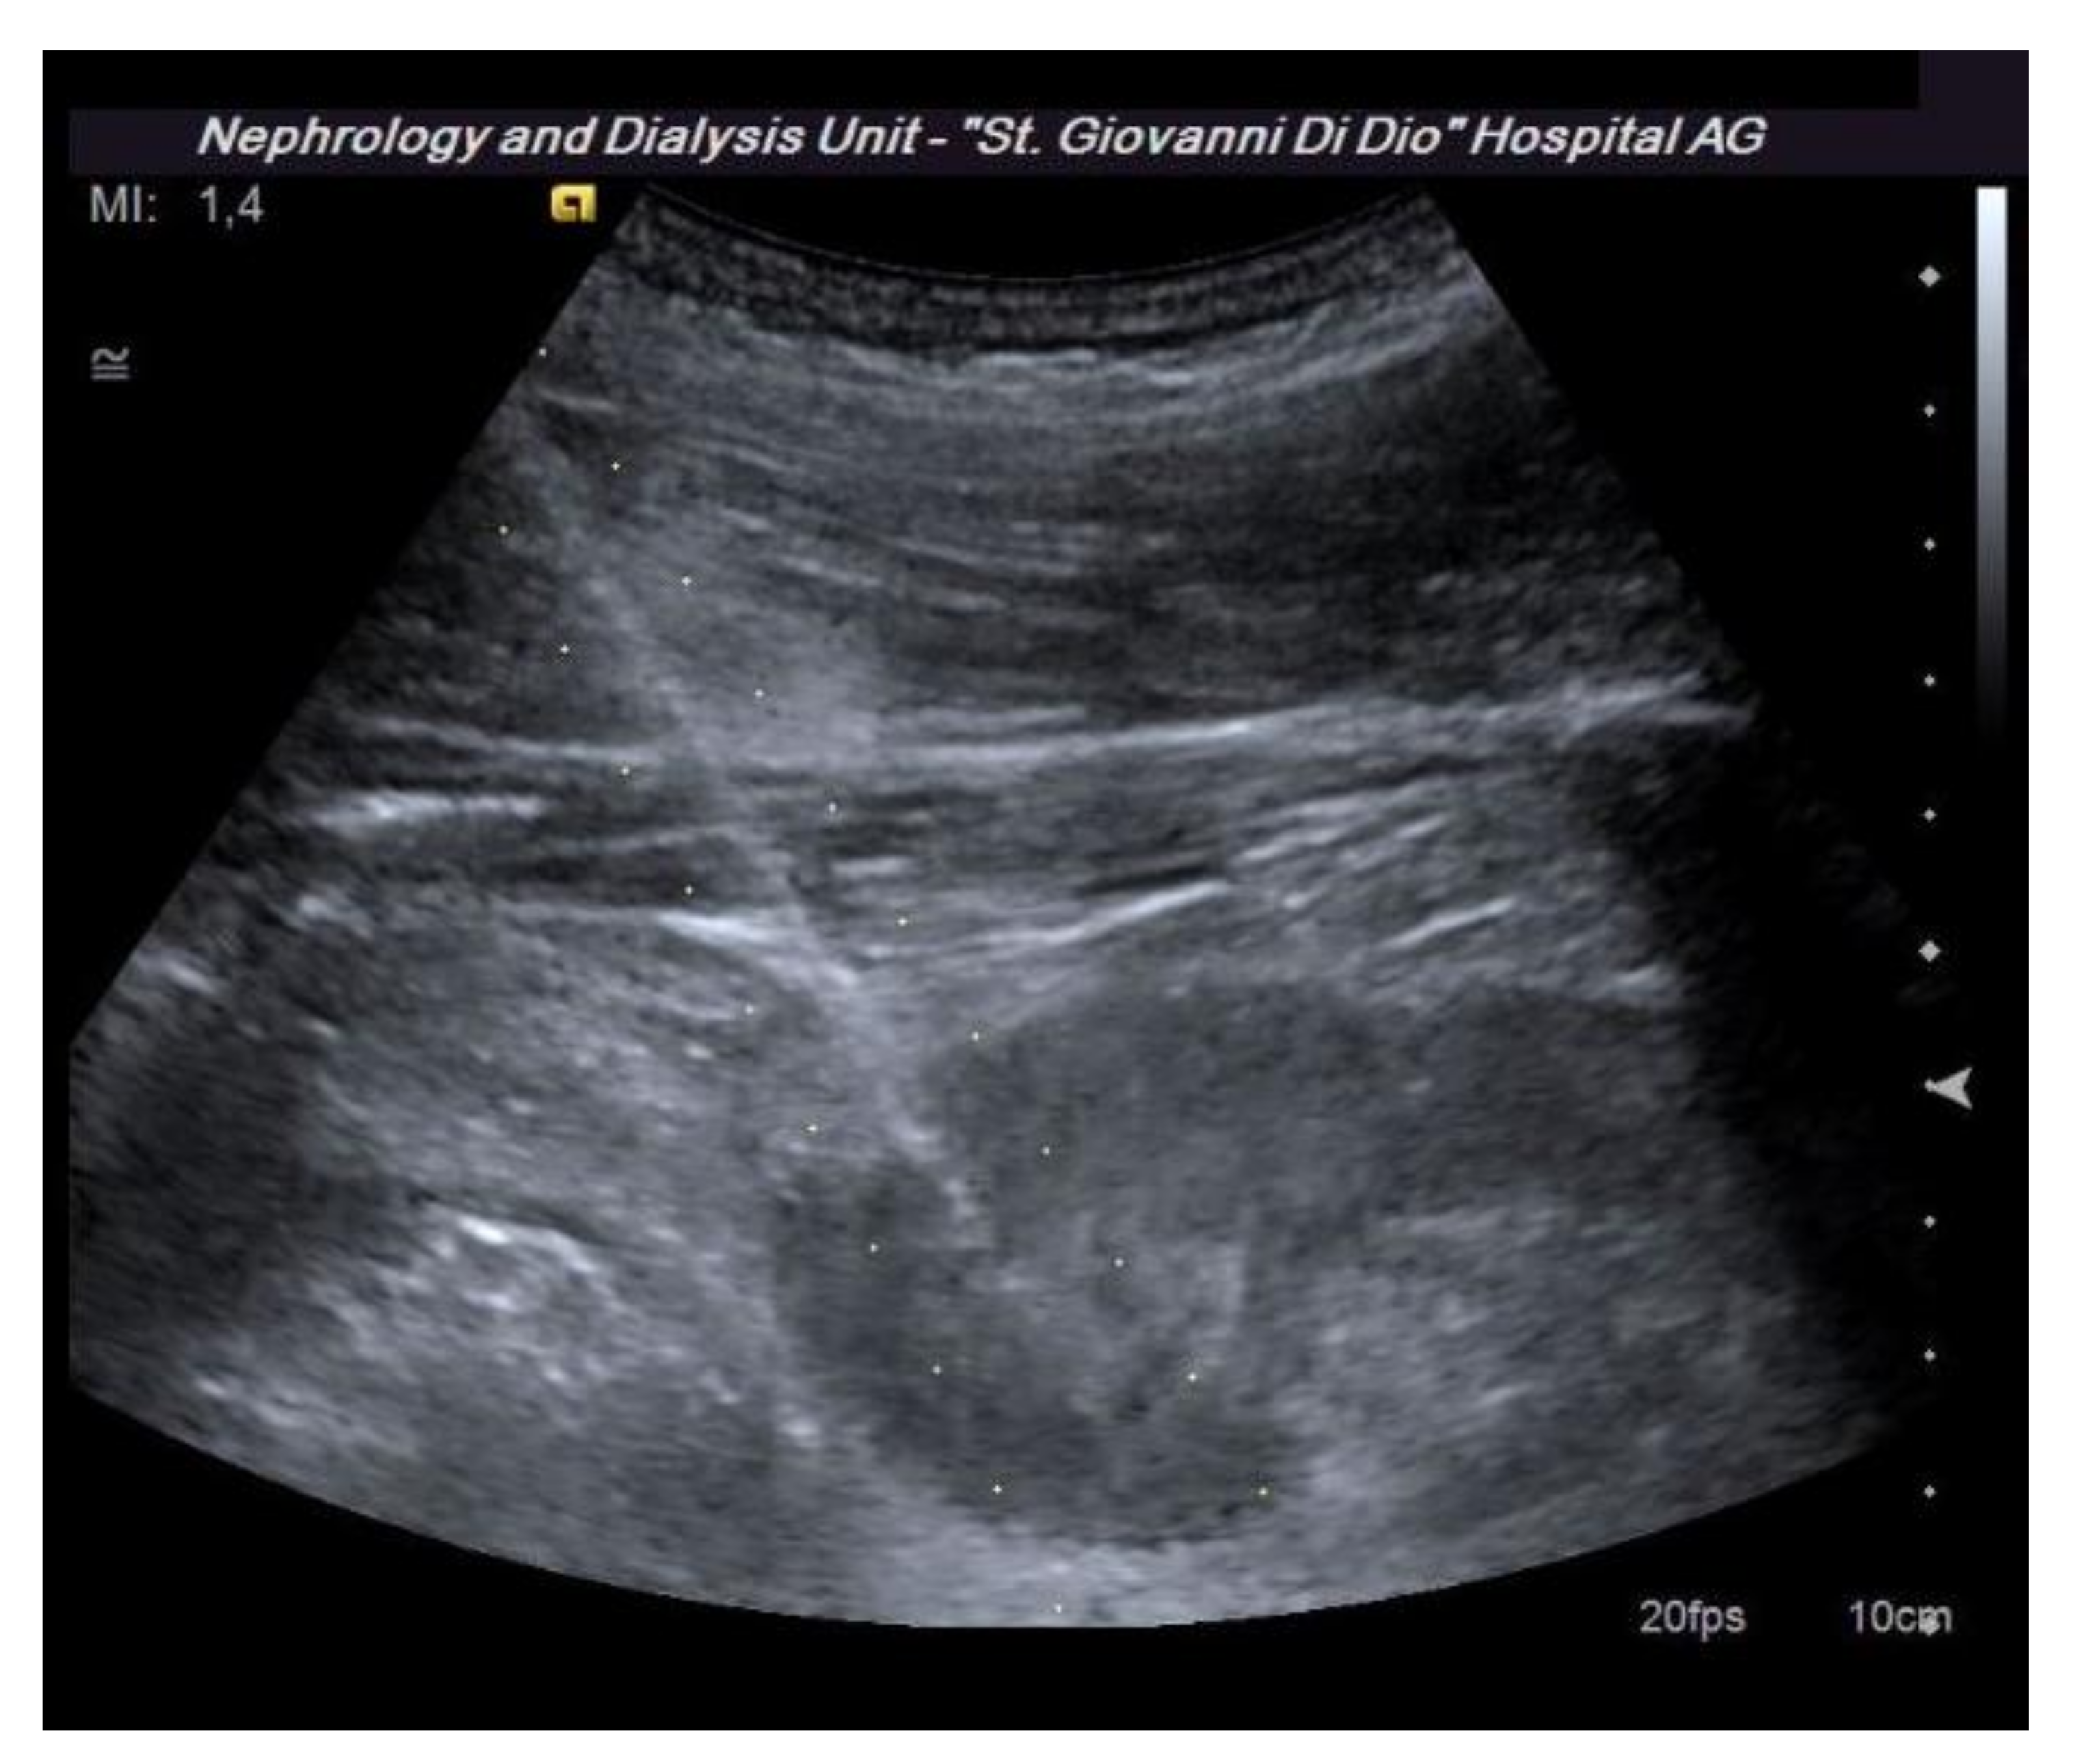

Before performing an ultrasound-guided PRB, it is advisable to perform a complete ultrasound examination of the kidneys in the same position as the procedure to evaluate the location of the kidney, its excursion during breathing, the cortical thickness, and the distance of the kidney from the skin surface. These data are useful to plan the procedure. Furthermore, this allows for the exclusion of anatomical variants (for example, horseshoe kidney), hydronephrosis, and cystic lesions, which may be contraindications for the procedure [16]. The examination must be completed with an ECD assessment to rule out the presence of vessels along the presumed path of the needle (Figure 3). Vascular abnormalities are reported in up to 10% of patients who undergo renal biopsy, and this may explain the reduction in complications observed when an ECD study preceded the procedure [15].

Figure 3.

The dotted lines show the expected trajectory of the needle when correctly fixed to the appropriate support. At the lower pole of the kidney, the site of the biopsy, there is an abnormal vascular formation that would have been crossed by the needle if it had not been recognized.